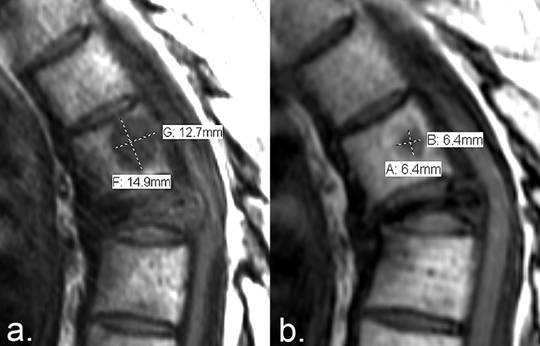

Figure 6

Quantitative measurement of PR using the MDA criteria. (a) T1-weighted sagittal MRI of the thoracic spine of a patient with multiple myeloma demonstrates a lesion with abnormally low T1 signal intensity in the T5 vertebral body. (b) Seven months later, fat reconstitution occurred around the periphery of the lesion, resulting in a decrease in the size of the metastasis. The sum of the perpendicular dimensions of the lesion has decreased from 27.6 mm to 12.8 mm (a 52% reduction in size), qualifying as partial response according to the MDA criteria (≥ 50% reduction required). The metastasis to the severely compressed T6 vertebral body is an example of a lesion that remains unmeasurable with anatomic response criteria.